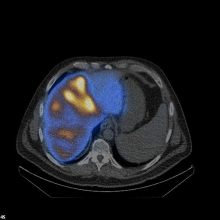

Image: Spect/low-dose CT showing tumor-oriented deposition of the 90Yttrium-labelled SIR-Spheres® in the right liver lobe in a patient with liver metastases from colorectal cancer.